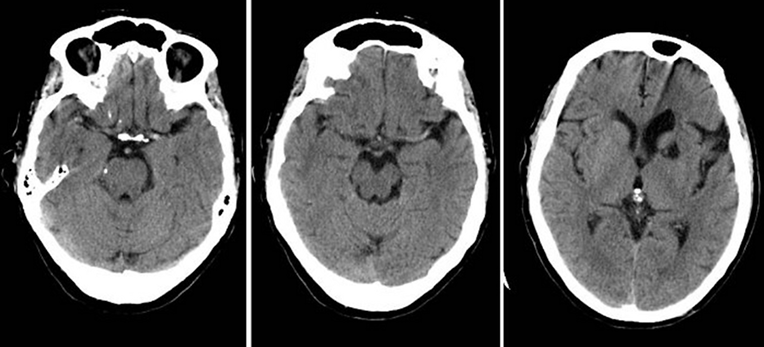

Explainable AI changes this. It shows the logic behind each detection, making it easier for specialists to verify findings. This transparency is especially important for identifying hypodense lesions, which often require careful evaluation due to their subtle appearances across CT & MRI scans in various anatomical regions due to their subtle contrast differences.

Hypodense lesions can be difficult to identify because they share almost visual similarities with the surrounding tissue. Even experienced radiologists may spend significant time reviewing multiple slices of a scan.

AI imaging applications assist in speeding up this process—but only if the accurate data behind them is correct. The strength of any AI model depends on the quality of its training data. When the segmentation is flawed or inconsistent, the model’s output becomes unreliable. This is why high-quality AI segmentation is essential. It ensures every pixel and boundary is segmented with precision. Hypodense lesions can indicate different pathologies depending on the organ, ranging from cerebral infarcts to hepatic cysts, splenic lesions, renal abnormalities, or soft-tissue changes. AI models must be trained on diverse, explainable datasets that reflect this anatomical variability.